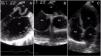

A 65-year-old woman was admitted to the hospital with fever and decompensated heart failure. She had long-lasting peripheral venous insufficiency and had been experiencing heart failure symptoms for six months. She had no history of hypertension, diabetes mellitus, coronary heart disease, atrial fibrillation, stroke or transient ischemic attack. Six days after admission, she developed acute pulmonary edema. A transesophageal echocardiography (TEE) revealed severe left ventricular dysfunction and an intracardiac thrombus measuring 5-6 cm, traversing a small patent foramen ovale (PFO) (Figure 1A). Unfractionated heparin was promptly initiated. Nevertheless, one week later, she woke up aphasic with right-sided hemiparesis. A brain computed tomography scan showed a left hemispheric stroke, while the patient's blood work, a cervical duplex scan and cardiac catheterization revealed no significant findings. The TEE was repeated and a smaller thrombus found (Figure 1B). Two months after discharge, the thrombus was undetectable (Figure 1C).

PFO is not considered to be a major cause of cardioembolic stroke, especially in the elderly, since other potential causes exist. Our case, however, shows that a causative thrombus resulting from a paradoxical PFO embolism could be detected before giving rise to a stroke. This case is important as it allowed direct thrombus imaging within the PFO before it led to a stroke, which is not always possible, as well as revealing a smaller thrombus trapped inside the PFO after the stroke. The first thrombus visualized probably arose from the venous system of the lower limbs and passed through a small ostium, giving us the exceptional opportunity to prove the stroke's cardioembolic etiology through a PFO in an elderly patient.